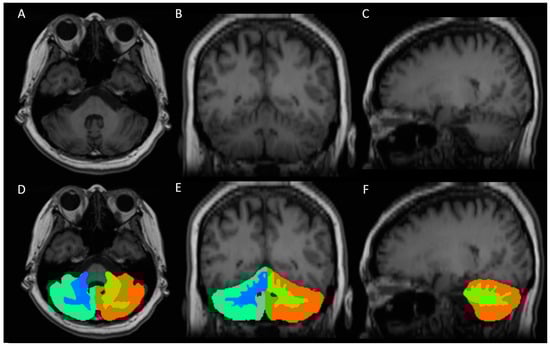

Quantitative volumetric analysis was performed using FreeSurfer software (version 7.1.0), which is an established and widely used approach for brain segmentation [32]. The recon-all pipeline, which involves intensity normalization, skull-stripping, motion correction, affine registration to the template, and probabilistic atlas-based segmentation, was employed for subcortical segmentation and to acquire left and right cerebellar gray and white matter volumes and whole-brain volume (Figure 2). One neuroradiologist (D.Y.-T.C.) reviewed the automatic subcortical segmentation to ensure alignment with the intended anatomical regions. Subjects with significant deviations in segmentation or inconsistencies between the volume of interest in the spectral study were excluded from the analysis. During the volumetric analysis of the brain using FreeSurfer, substantial variation in head and brain size, including the cerebellum, was observed between the individuals, particularly between males and females. To account for this variation, we normalized the volumes of cerebellar gray and white matter by dividing them by the total brain volume, which was also obtained using FreeSurfer.

Figure 2.

A representative case of cerebellar segmentation. (A–C) Axial, coronal, and sagittal view of T1-weighted high-resolution image, respectively. (D–F) Axial, coronal, and sagittal view of right cerebellar gray matter mask (cyan), right cerebellar white matter mask (blue), left cerebellar gray matter mask (orange), and left cerebellar white matter mask (green), respectively.